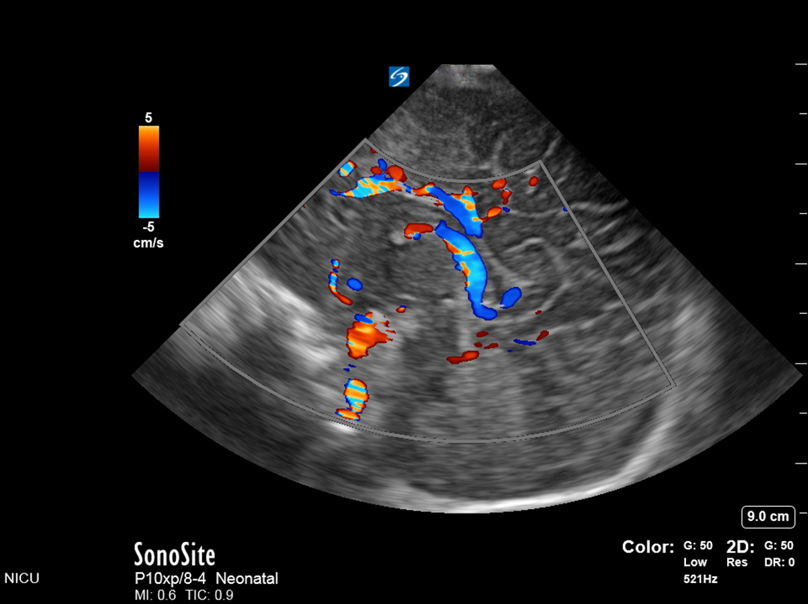

Neonatology IVH Summary Doppler Image